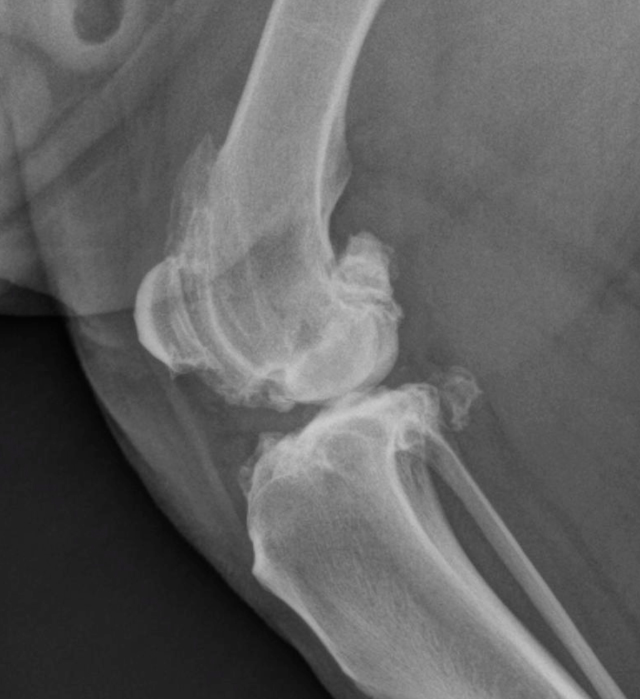

Identifying and Managing Your Pet's Arthritis

Knee joint with arthritis.